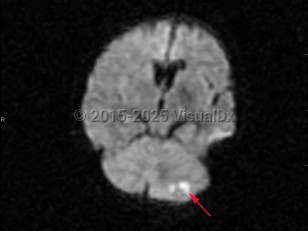

Risk factors for cerebellar strokes are the same as for other cerebrovascular pathologies: hypertension, hyperlipidemia, diabetes, cardioembolic risks such as atrial fibrillation, and tobacco abuse are chief among them. Cerebellar hemorrhages can also be caused by a rupture of vascular malformations; hereditary hemorrhagic telangiectasia (HHT) is a particular risk factor. Rupture of vascular malformations is a more likely cause in children. Other risk factors for cerebellar hemorrhages include sympathomimetic abuse such as cocaine use. Increased urinary sodium is associated with increased risk.

Related topic: drug-induced stroke